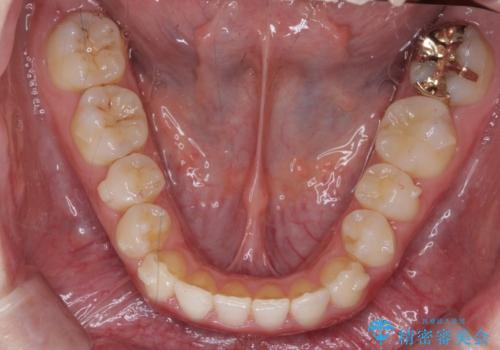

下の歯のがたつき 上より気になる

- 前歯のがたつきが気になって来院。

下の歯のがたつきが上よりも多い状態でした。

下の前歯は上の歯の内側にあるため、外に並べることができないため、上ほど簡単ではありません。

すき間をしっかりとって並べる必要があります。

今回は、下の歯を健康に支障が出ない範囲でわずかに削合し、並べるようにしました。(ディスキングといいます)

前歯のがたつきもしっかり治り、喜んでいただけました。

下の親知らずは虫歯になっていたため矯正前に抜歯しています。